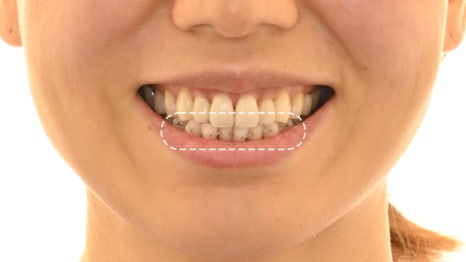

부분교정 치료가 끝나고 나서

가지런한 치열로 제자리를 찾아갔습니다.

이제는 어느 방향에서 보더라도

윗니가 아랫니를 살짝 덮고 있습니다.

사소하게 틀어져 있다 할지라도

오래 방치할수록 조금씩 틀어질 수 있습니다.

이가 틀어지면 틀어질수록

충치, 치주질환이 나타날 확률이 높아지고,

구강 상태를 건강히 유지하기 어려워집니다.

현재 틀어짐으로 인하여 불편함을 겪고 있다면

한 번쯤 검진을 받아볼 것을 권장합니다.